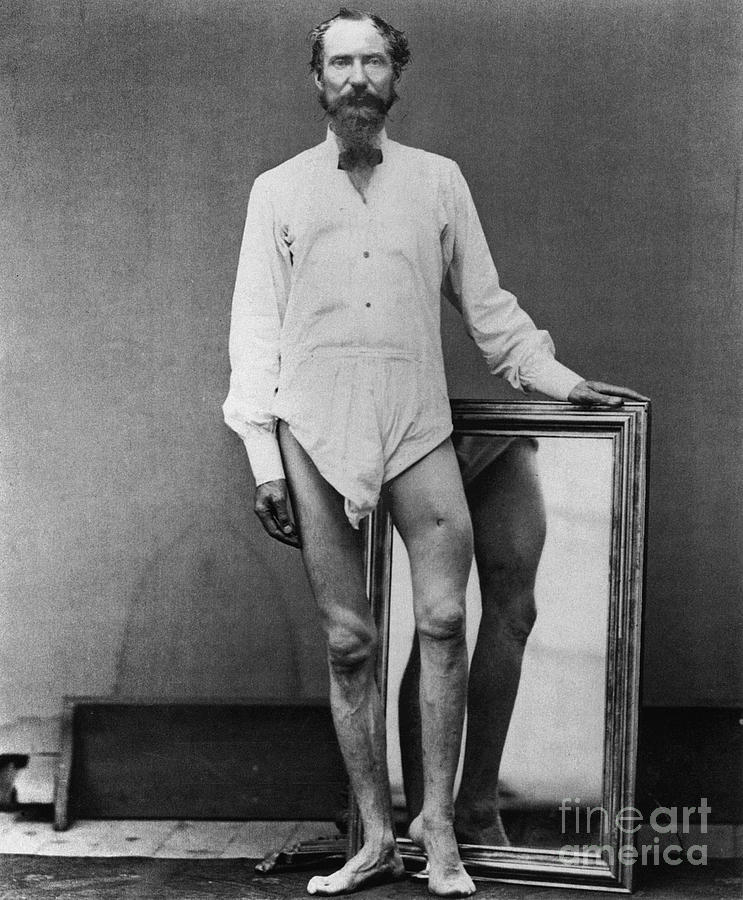

Civil War: Gunshot Wound Photograph by Granger

Treatise on Gun-Shot Wounds, on Inflammation, Erysipelas, and …